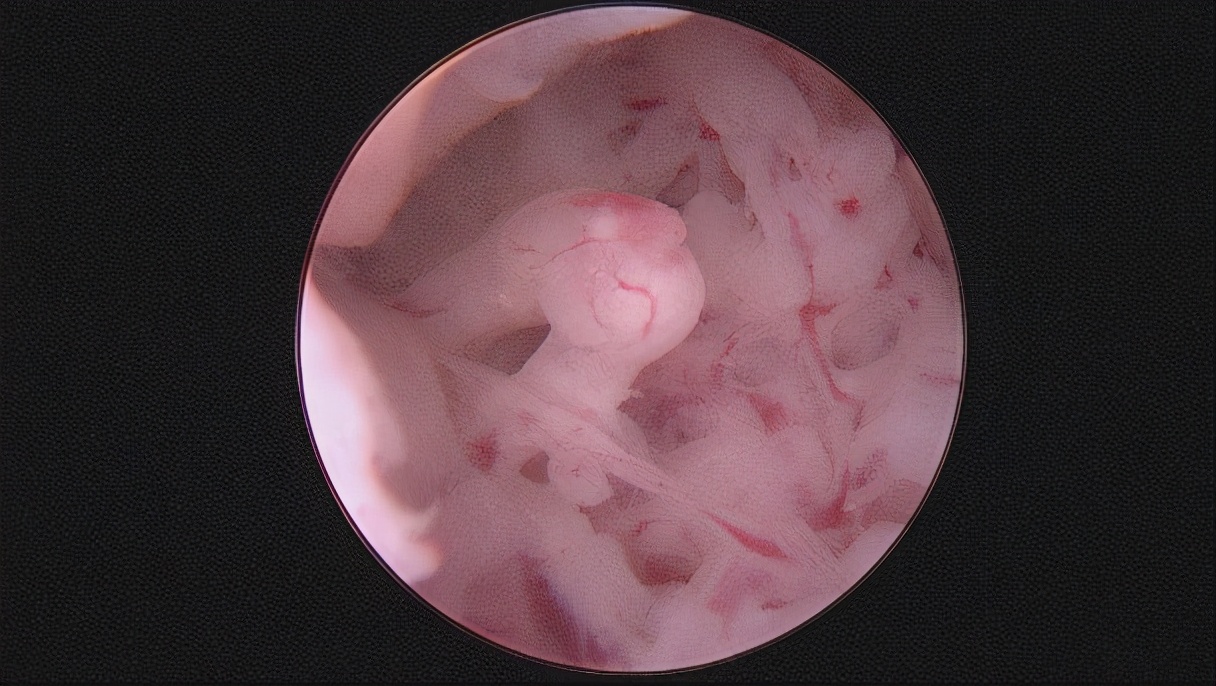

图二:整复好的宫腔

图三:宫形环支撑

注:宫腔粘连手术是关键,术后还要综合治疗,宫腔放置球囊和宫形环支撑宫腔。配合防黏连的凝胶以及雌激素药物让子宫内膜更好的生长。